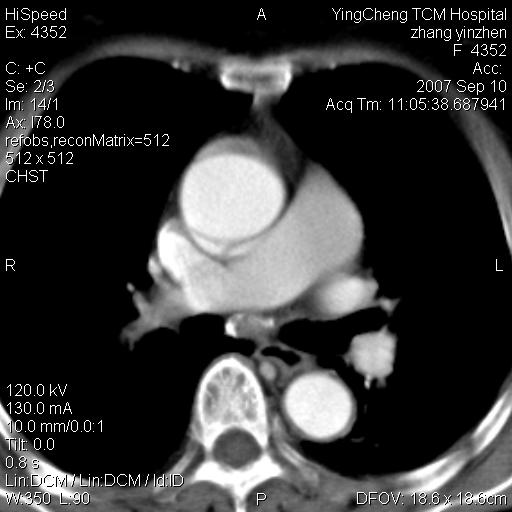

以下是引用卜一在2007-9-18 14:41:00的发言:[br]右肺肿块:毛刺+胸膜凹陷征+供血血管+浅分叶+强化。支持:周围性肺癌 !另:左侧甲状腺腺瘤!

以下是引用夏季在2007-9-18 11:00:00的发言:[br]1。右肺肿块,周围有短毛刺,肺门侧有血管与其相连,胸壁侧有胸膜凹陷征,考虑周围性肺癌 2。左侧甲状腺软组织肿块,内有高密度钙化灶,考虑左侧甲状腺腺瘤。